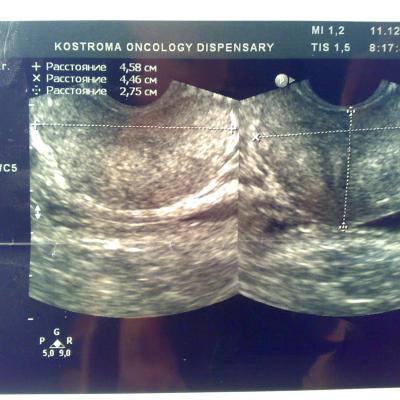

Доброго времени суток. В начале декабря сходил в банное заведение, употребил там пиво, вечером был сексуальный контакт с постоянной партнершей, на утро у обоих появилось жжение при мочеиспускании, у меня покраснение губок полового члена, умеренные выделения прозрачные, анализы крови и мочи в норме, ПЦР у обоих отрицательные. У девушки соэ 28, лейкоциты в моче выше 200, у меня все в норме, бак посев отделяемого из уретры выявил обильный рост Ешерихии коли, принимал внутремышечно Цефотаксим по 1г 2раза в день в течении 5 дней, во время лечения появилось жжение и дискомфорт в промежности. Трузи показало увеличение простаты, расширенные семенные пузырьки около 3 мм, кальцинатов и инфильтратов нет, в область мочевого пузыря не вдается, остаточное количество мочи около 10 мл, кол лейкоцитов в отделяемом из уретры 5-8 в поле зрения. Сейчас принимаю по назначению уролога Нолицин 400 мг по таблетке два раза в день, Палин 250 мг по 1 два раза и азитромицин 250 по одной раз в сутки, свечи на ночь Простатилен курс на 10 дней, уже прошло восемь массажей улучшение незначительное, симптомы в обшей картине сохраняются, железа со слов уролога стала более упругой и меньших размеров. У меня стала страдать эрекция, полной уже нет около 2 месяцев. После эякуляции хочется мочится, неприятные скребущиеся ощущения в промежности, сперма раньше выстреливала, а сейчас вытекает, выстреливает только первая порция, появились боли в мошонке слева, особенно после массажа, подскажите пожалуйста что делать, как лечится, какие еще анализы сдавать. Прикреплены снимки узи.Заранее благодарен.